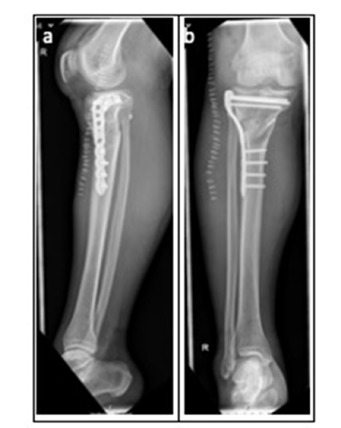

Final intraoperative fluoroscopic imaging confirmed correct implant placement and satisfactory osteotomy alignment (Figure 5).

Figure 5:Postoperative Radiographic Evaluation. a. Lateral radiograph demonstrating plate osteosynthesis of the proximal tibia and TightRope fixation of the proximal tibiofibular joint. b. Anteroposterior postoperative radiograph showing the same plate osteosynthesis and TightRope fixation in situ.

Following the osteotomy, a significant improvement in the mechanical limb axis was achieved. Proper anatomical repositioning of the proximal fibula within the tibiofibular joint was verified. During the inpatient stay, the patient was able to mobilize independently using forearm crutches. A full-length standing radiograph is scheduled for postoperative outpatient follow-up.